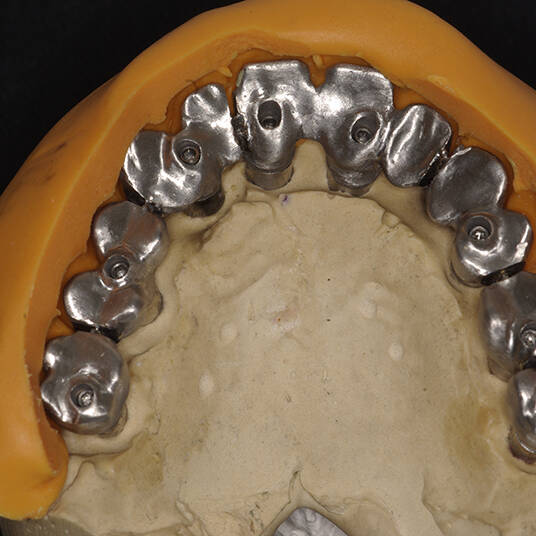

- Planejamento Digital: Com o auxílio de tecnologias como tomografias e softwares 3D, a posição dos implantes é planejada com precisão.

- Cirurgia de Instalação dos Implantes: Os implantes são fixados no osso maxilar ou mandibular, proporcionando uma base sólida para a prótese.